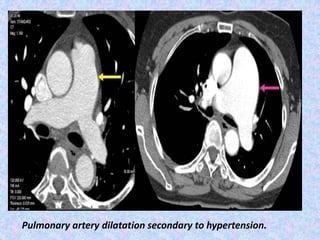

Pulmonary artery dilatation secondary to hypertension.

Pulmonary artery dilatationsecondary to hypertension.

Pulmonary hypertension.

Pulmonary hypertension (PH) is an increase of blood pressure in the

pulmonary artery, pulmonary vein, or pulmonary capillaries,

together known as the lung vasculature, leading to shortness of

breath, dizziness, fainting, leg swelling and other symptoms.

Pulmonary hypertension is usually occur secondary to emphysema.